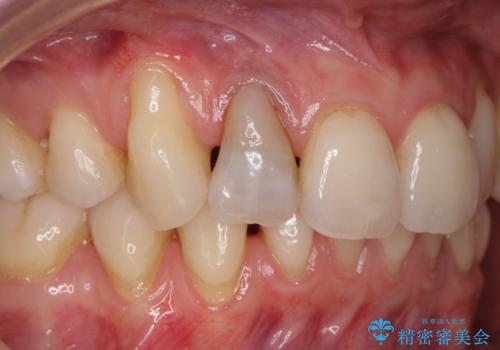

歯と歯の間の虫歯 セラミックインレーでの治療

- 検査の結果虫歯が見つかった患者様です。

レントゲン画像と視診から詰め物で対応可能と判断したためインレーでの修復をしていきます。